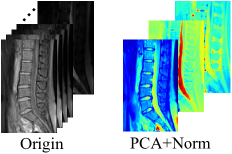

Refer to caption

Figure 2: Data transformation from 31 channels to 3 channels after PCA processing. Origin data is collected from 6 volunteers. The dataset shows vertebral area of human beings.

The left part of Fig. 2 shows a sample of the origin 31-channel images and the transformation result after PCA and normalization processing. Fig. 3 shows all of the 31 singular values of X𝑋X which is also the square root of eigenvalues of XXT𝑋superscript𝑋𝑇XX^{T} from all of the six samples of the datasets. The first three singular values take the weights of all the singular values in more than 99.9%percent99.999.9\%. That means the transformation is more efficient and meaningful. The largest three singular values of X𝑋X can almost represent all of the origin information in the raw sample equivilently.

The fMRI datasets have a broad range of pixel intensities. The different ranges significantly influence the accuracy of segmentation. Even after PCA processing, the ranges of the three channels are still quite irregular. To locate the maximal and minimal elements among the three channels, we normalize the three channels to a range of (0,255), which is the range of 8-bit images. The right part of Fig. 2 illustrate the sample condition after PCA and normalization.